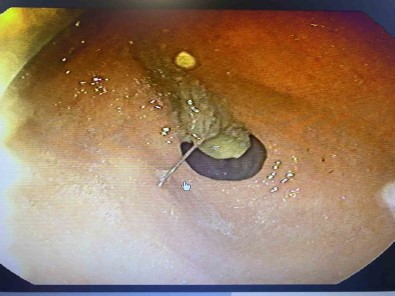

Daha sonra bir hapsirma gelismis, aniden nefes çekme olayi oldugu için yemek borusuna bu igne kaçmis. Bir ihtimal bu soluk borusuna da gidebilirdi böyle ani nefes almalarda o zaman soluk borusunun incelenmesi gerekirdi, akcigere kaçardi. Bu sartlarda yemek borusundan midesine dogru ilerleme olmus. Bize basvurdugunda bu isin üzerinden 2-3 saat geçmisti, igne yavas yavas ilerlemisti. Biz acil servilerde yaptigimiz görüntülemelerde ignenin henüz daha midede oldugunu, daha fazla ileriyle gitmedigini gördük. Akabinde hastamizi endoskopi ünitemize aldik, burada yaptigimiz endoskopide de tam mide çikisinda mide mukozasi dedigimiz en iç tabasina saplanmis sekilde gida artiklarinin arasinda durdugunun gördük. Zor da olsa özel aletlerimizi kullanarak ignemizi tuttuk, daha sonra endoskopi kanalinin içinden hastamiza herhangi bir zarar vermeden disariya çikarttik. Bu ignenin hastamiza bu asamaya kadar herhangi bir zarar vermedigini yemek borusunda, midesinde yirtilma yapmadigini gördük" diye konustu.

"Ignemiz 3-4 cm boyutunda toplu bir igneydi"

Ignenin daha ileri bir noktaya gitmesi durumunda ameliyat gerekliligi olusabilecegini söyleyen Op. Dr. Çalikoglu, “Igne saplandigi yerden daha da ilerlese midede, ince bagirsakta küçük de olsa delinmelere, bir ihtimal ameliyatla çikarilmasi gerekliligi durumlarina ulasabilirdi. Çok sükür ki hastamiz sansliydi, bize dogru zamanda gelmisti. Oyuncaklardaki küçük boncuklar, nazar boncuklari, tespih tanesi, nohut, küçük parçali oyuncaklar olabilir. Bunlar hep çocuklarimizin özellikle yemek borusuna gitse bile soluk borusuna giderek çok ciddi nefes durmalari ve sagligi tehdit edici durumlar olusabiliyor. Piyasada açikta olan bazi deterjan ürünleri olabiliyor, bunlari su siselerine biriktirenler ve ya evde ne kadar deterjan kullanacaksa onlari bardaga koyup bekletenler olabiliyor bunlari da çocuklarimiz, büyüklerimiz yanlislikla içebiliyor. Bunlara azami dikkat etmemiz lazim. Igne tutacaksa agzinda, vidalama yapacaksa tamir yaparken agzina çivi almalar olabiliyor. Agzimizi bunlarda kullanmamamiz lazim çünkü aniden hapsirma, öksürmeyle ve ya kayma sekliden biz bunlari tutamiyoruz. Yemek borumuza dogru inmeye basliyor. Ignemiz 3-4 cm boyutunda toplu bir igneydi. Agirligi toplu tarafinda oldugu için ters dogru inmis, hastamizda bogazinda ve gögsünde acitmalar yapmis" ifadelerini kullandi.